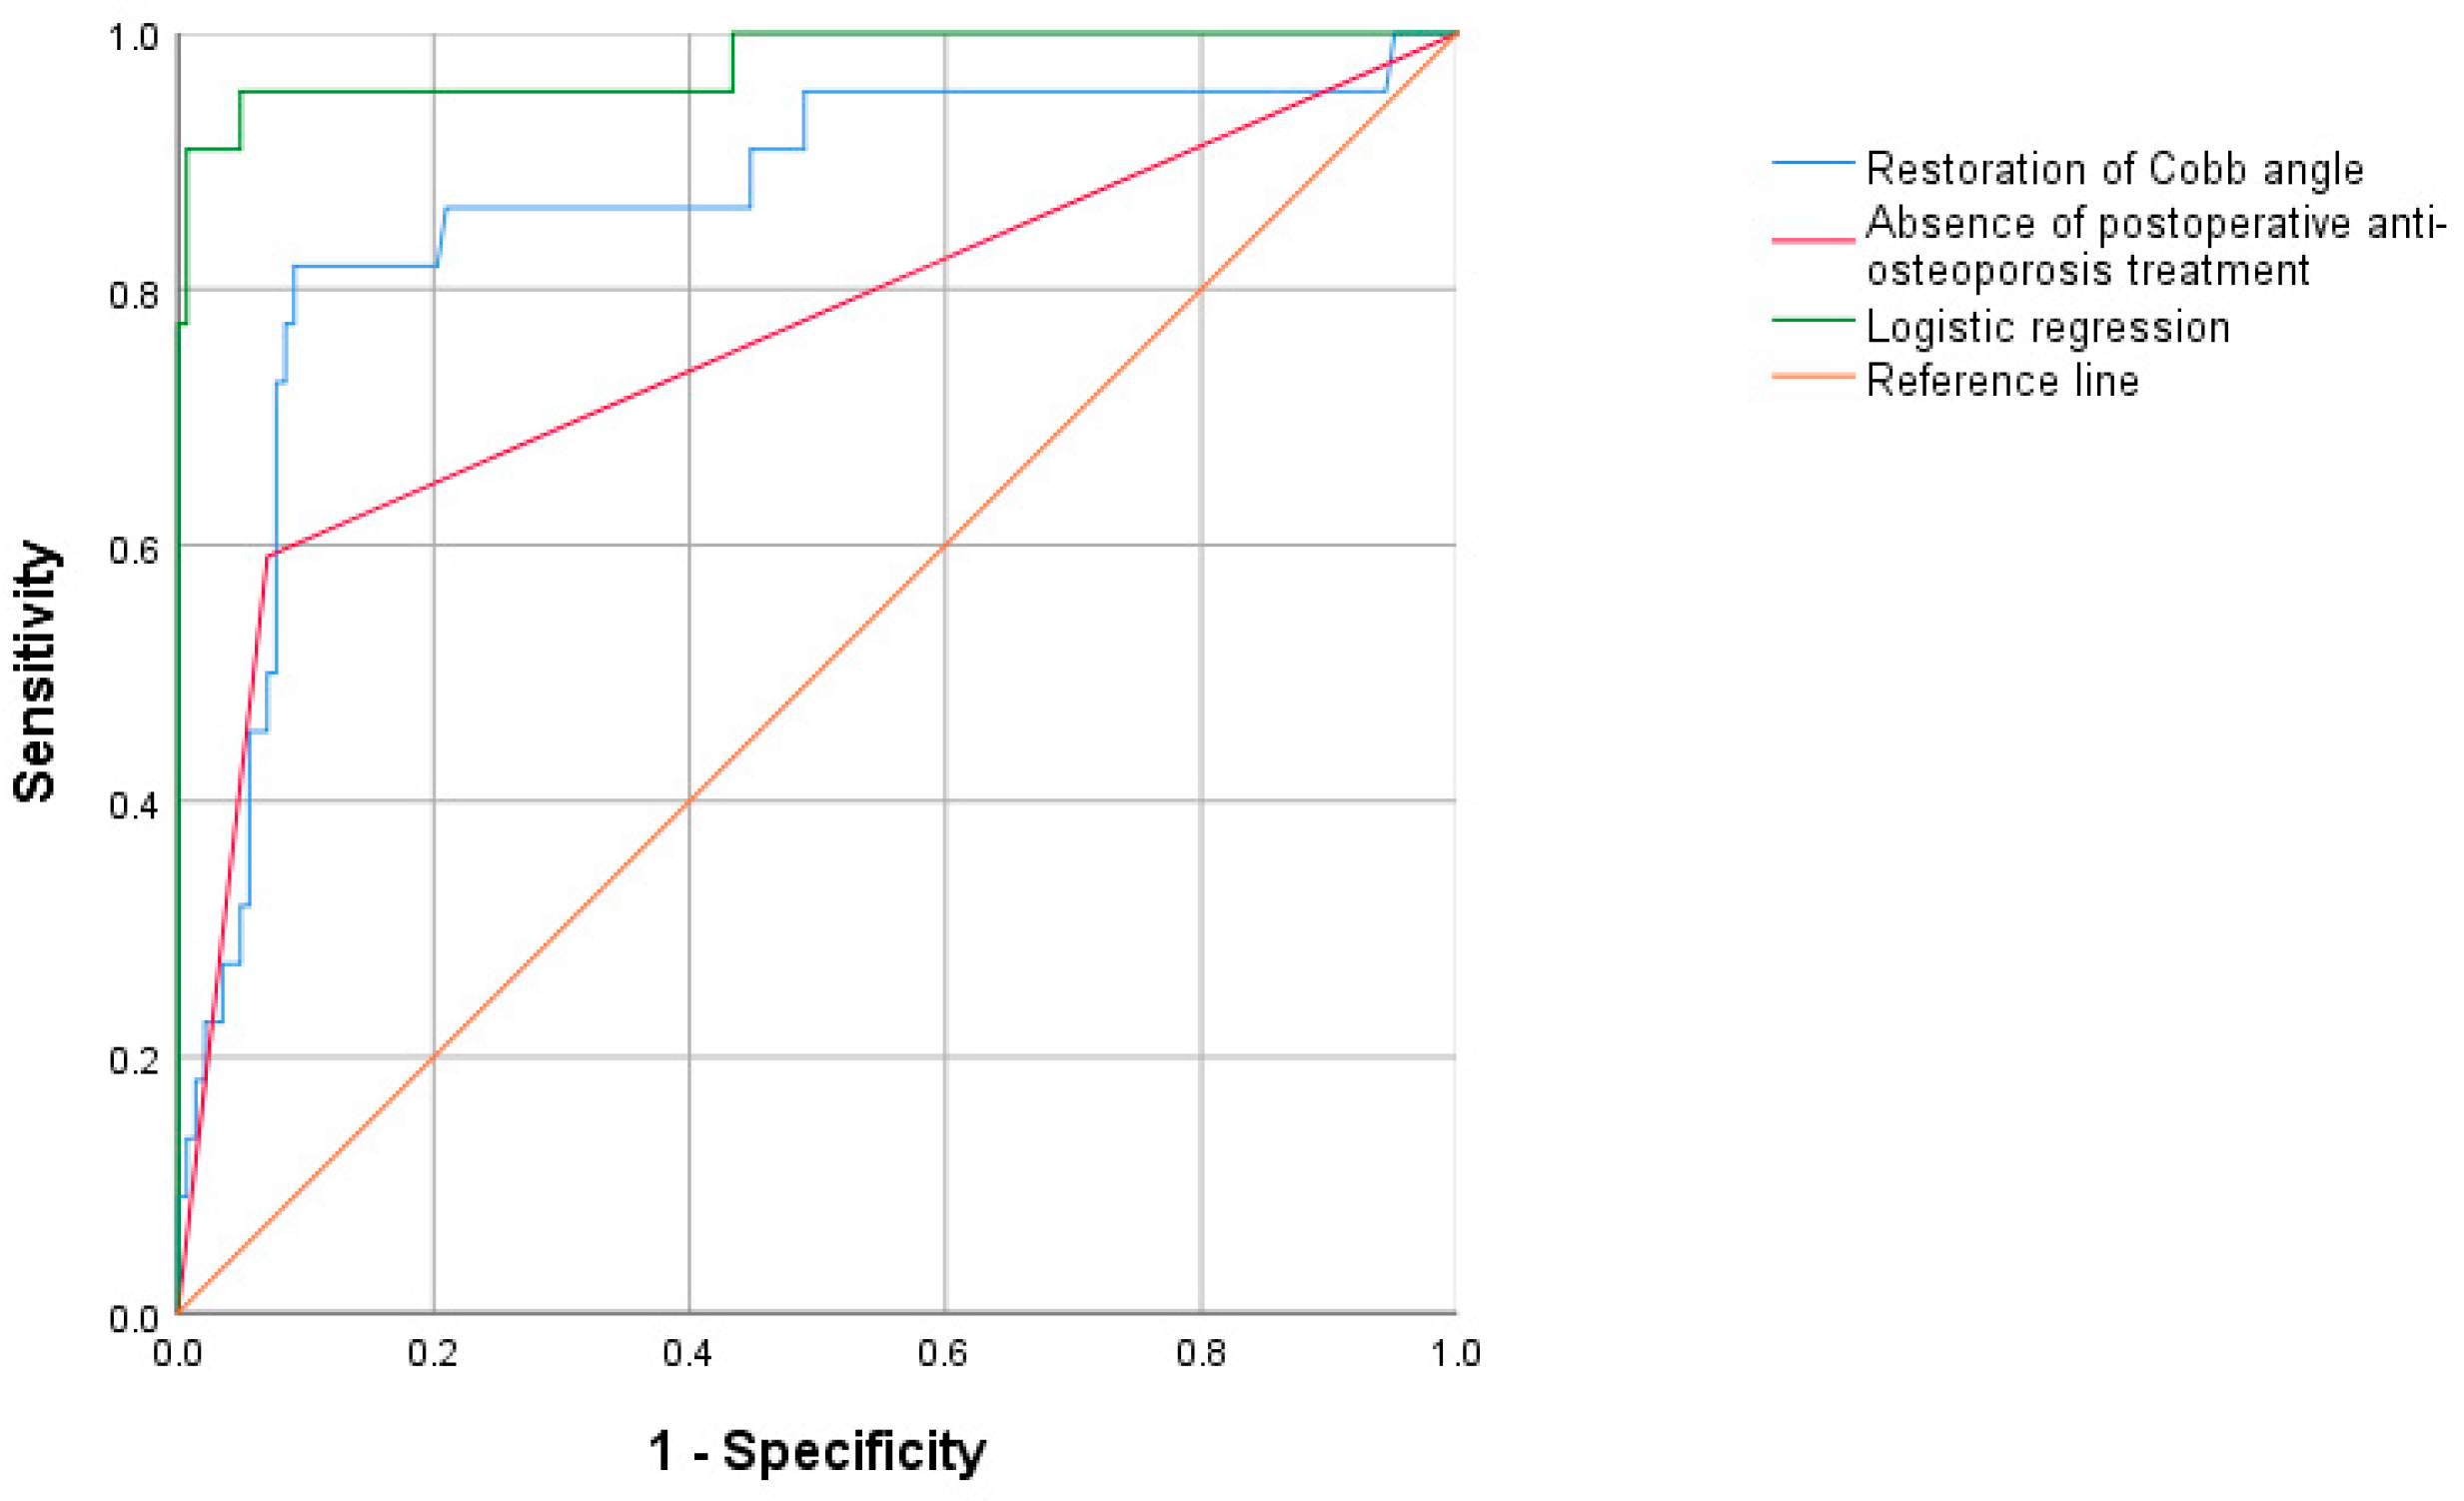

3.2.3. Receiver Operating Characteristic (ROC) Curve

| AUC | p Value | 95% CI | Optimal Cutoff Value | Sensitivity | Specificity | Youden’s Index | |

| Restoration of Cobb angle | 0.863 | <0.001 | 0.768~0.958 | 36.432 | 0.818 | 0.909 | 0.727 |

| Absence of postoperative anti-osteoporosis treatment | 0.760 | <0.001 | 0.631~0.890 | - | 0.591 | 0.930 | 0.521 |

| Logistic regression | 0.977 | <0.001 | 0.939~1.000 | 0.955 | 0.951 | 0.906 |